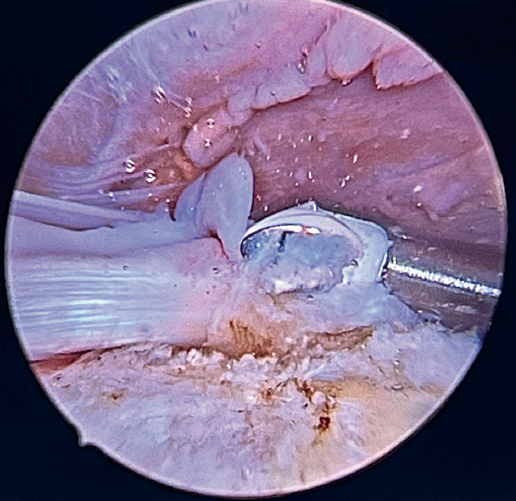

Tension-free repair of the supraspinatus tendon is then made, using the free thread left at the anchoring and taking advantage of the two sutures passed through and knotted to the proximal LPB fragment (Figures 8, 9 and 10).

The free suture remaining at the anchoring is passed through the anterolateral supraspinatus using a Scorpion® direct suture passer (Arthrex, Naples, FL, USA), as a sliding mattress suture over the implant.

One end of each of the sutures exiting the LPB is passed through the supraspinatus likewise using a Scorpion® direct suture passer (Arthrex, Naples, FL, USA). All the threads are left unknotted and are recovered through the anterior working portal so that they do not get in the way when working later on. Note that the two threads exiting the LPB and passing through the supraspinatus will not slide; it is therefore advisable to knot them and lower them later on with a knot pusher. This point allows repair of the anterior supraspinatus to be combined with fixation of the LPB in the anterolateral zone of the greater tuberosity.

A second anchorage loaded with two tapes is implanted at the same height as the first, but in a more posterior position. Again using direct suturing with mattress stitches, we repair the posterolateral part of the supraspinatus and even the anterior part of the infraspinatus, if necessary.

Having passed both the anterior and the posterior sutures, we proceed to knot, through the lateral portal with a working cannula, each of the sutures, starting posterior and ending anterior.

Finally, the anterolateral supraspinatus threads are used in combination with the posterolateral tapes to establish a more lateral double row with two direct anchorings that allow the threads to be threaded through two loops(Biocomposite SwiveLock® C 4.75 × 19.1 mm, Arthrex, Naples, FL, USA). This achieves a tension-free double row repair of the supraspinatus, covering the superior capsular repair made with the LPB (Figure 11).